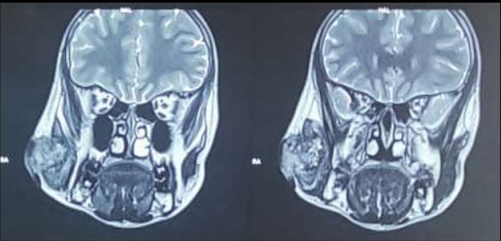

Patient was advised USG guided Fine Needle Biopsy (FNB) and MRI for right parotid swelling. FNB was suggestive of mucoepidermoid carcinoma. MRI showed lobulated mass involving right parotid region of size 3*3.4*4.7cm (AP*TRA*CC), right masseter muscle was involved. Laterally overlying skin and cutaneous tissues were involved, medially abutting right mandibular ramus. Diffuse fatty infiltration of right parotid gland with involvement of superficial lobe of parotid gland. Deep lobe and neurovascular bundle were unremarkable.

Figure 1: PREOPERATIVE

Figure 2